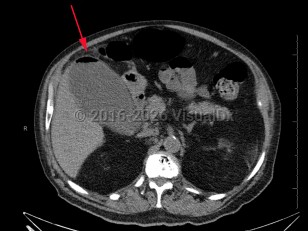

Emphysematous cholecystitis

Emphysematous cholecystitis is a rare variation of acute cholecystitis caused by secondary infection of the gallbladder wall with gas-forming bacteria such as Clostridium welchii, Clostridium perfringens, Escherichia coli, and Bacteroides fragilis as well as Pseudomonas, staphylococci, and streptococci. Men between the ages of 50 and 70 are most frequently affected. Type 2 diabetes and gallstones are common in affected patients. Emphysematous cholecystitis can also arise due to ischemia from atherosclerosis of the cystic artery.

Common presenting symptoms are similar to those for acute cholecystitis and include upper right quadrant abdominal pain, nausea, vomiting, and low-grade fever. On physical exam, abdominal wall crepitus may be palpated in the area overlying the gallbladder. Common complications include gangrene, perforation, pericholecystic abscess, and peritonitis. Uncommon complications include pneumoperitoneum.